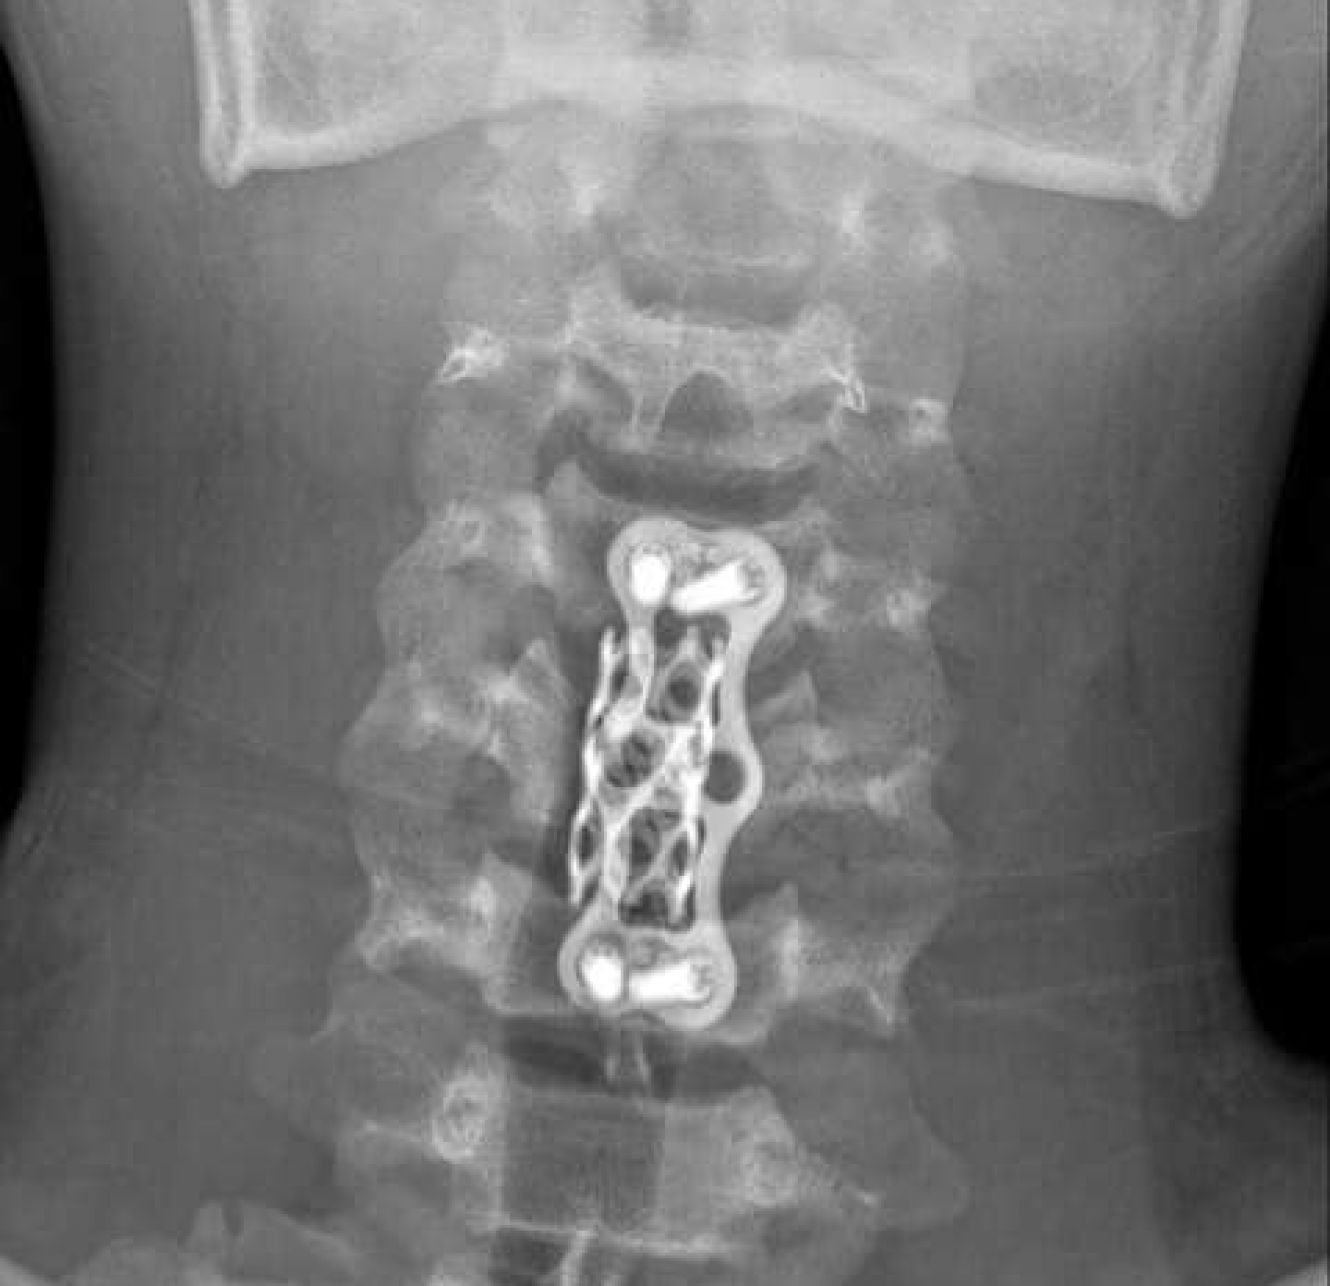

Пацієнту було видалено зруйновані кісні структури, усунено компресію (здавлювання) спинного мозку та корінців, замінено тіло зруйнованого хребця та проведено стабільну фіксацію. Якщо говорити немедичною мовою, то хребці скріплені пластинами з гвинтами, а для відновлення тіла хребця використано металевий імплант.